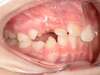

Avant

Après